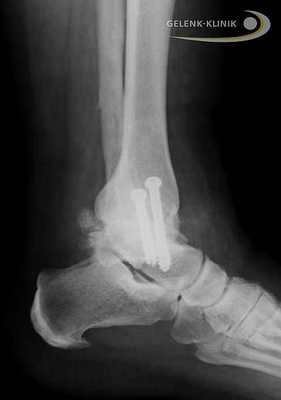

Артродез помогает восстановить безболезненность и потерянную подвижность. Данное вмешательство требует использования специальных винтов и интрамедуллярных гвоздей. Они фиксируют сустав до полной оссификации. © Gelenk-Klinik

Прочное важное для остеосинтеза костное соединение, закрепляется при помощи винтов либо пластин. Артроскопические вмешательства подразумевают лишь микроскопические разрезы на коже. Сохранение мягких тканей является является важным элементов в таком лечении: только при низком рубцевании, в будущем возможно эндопротезирование.